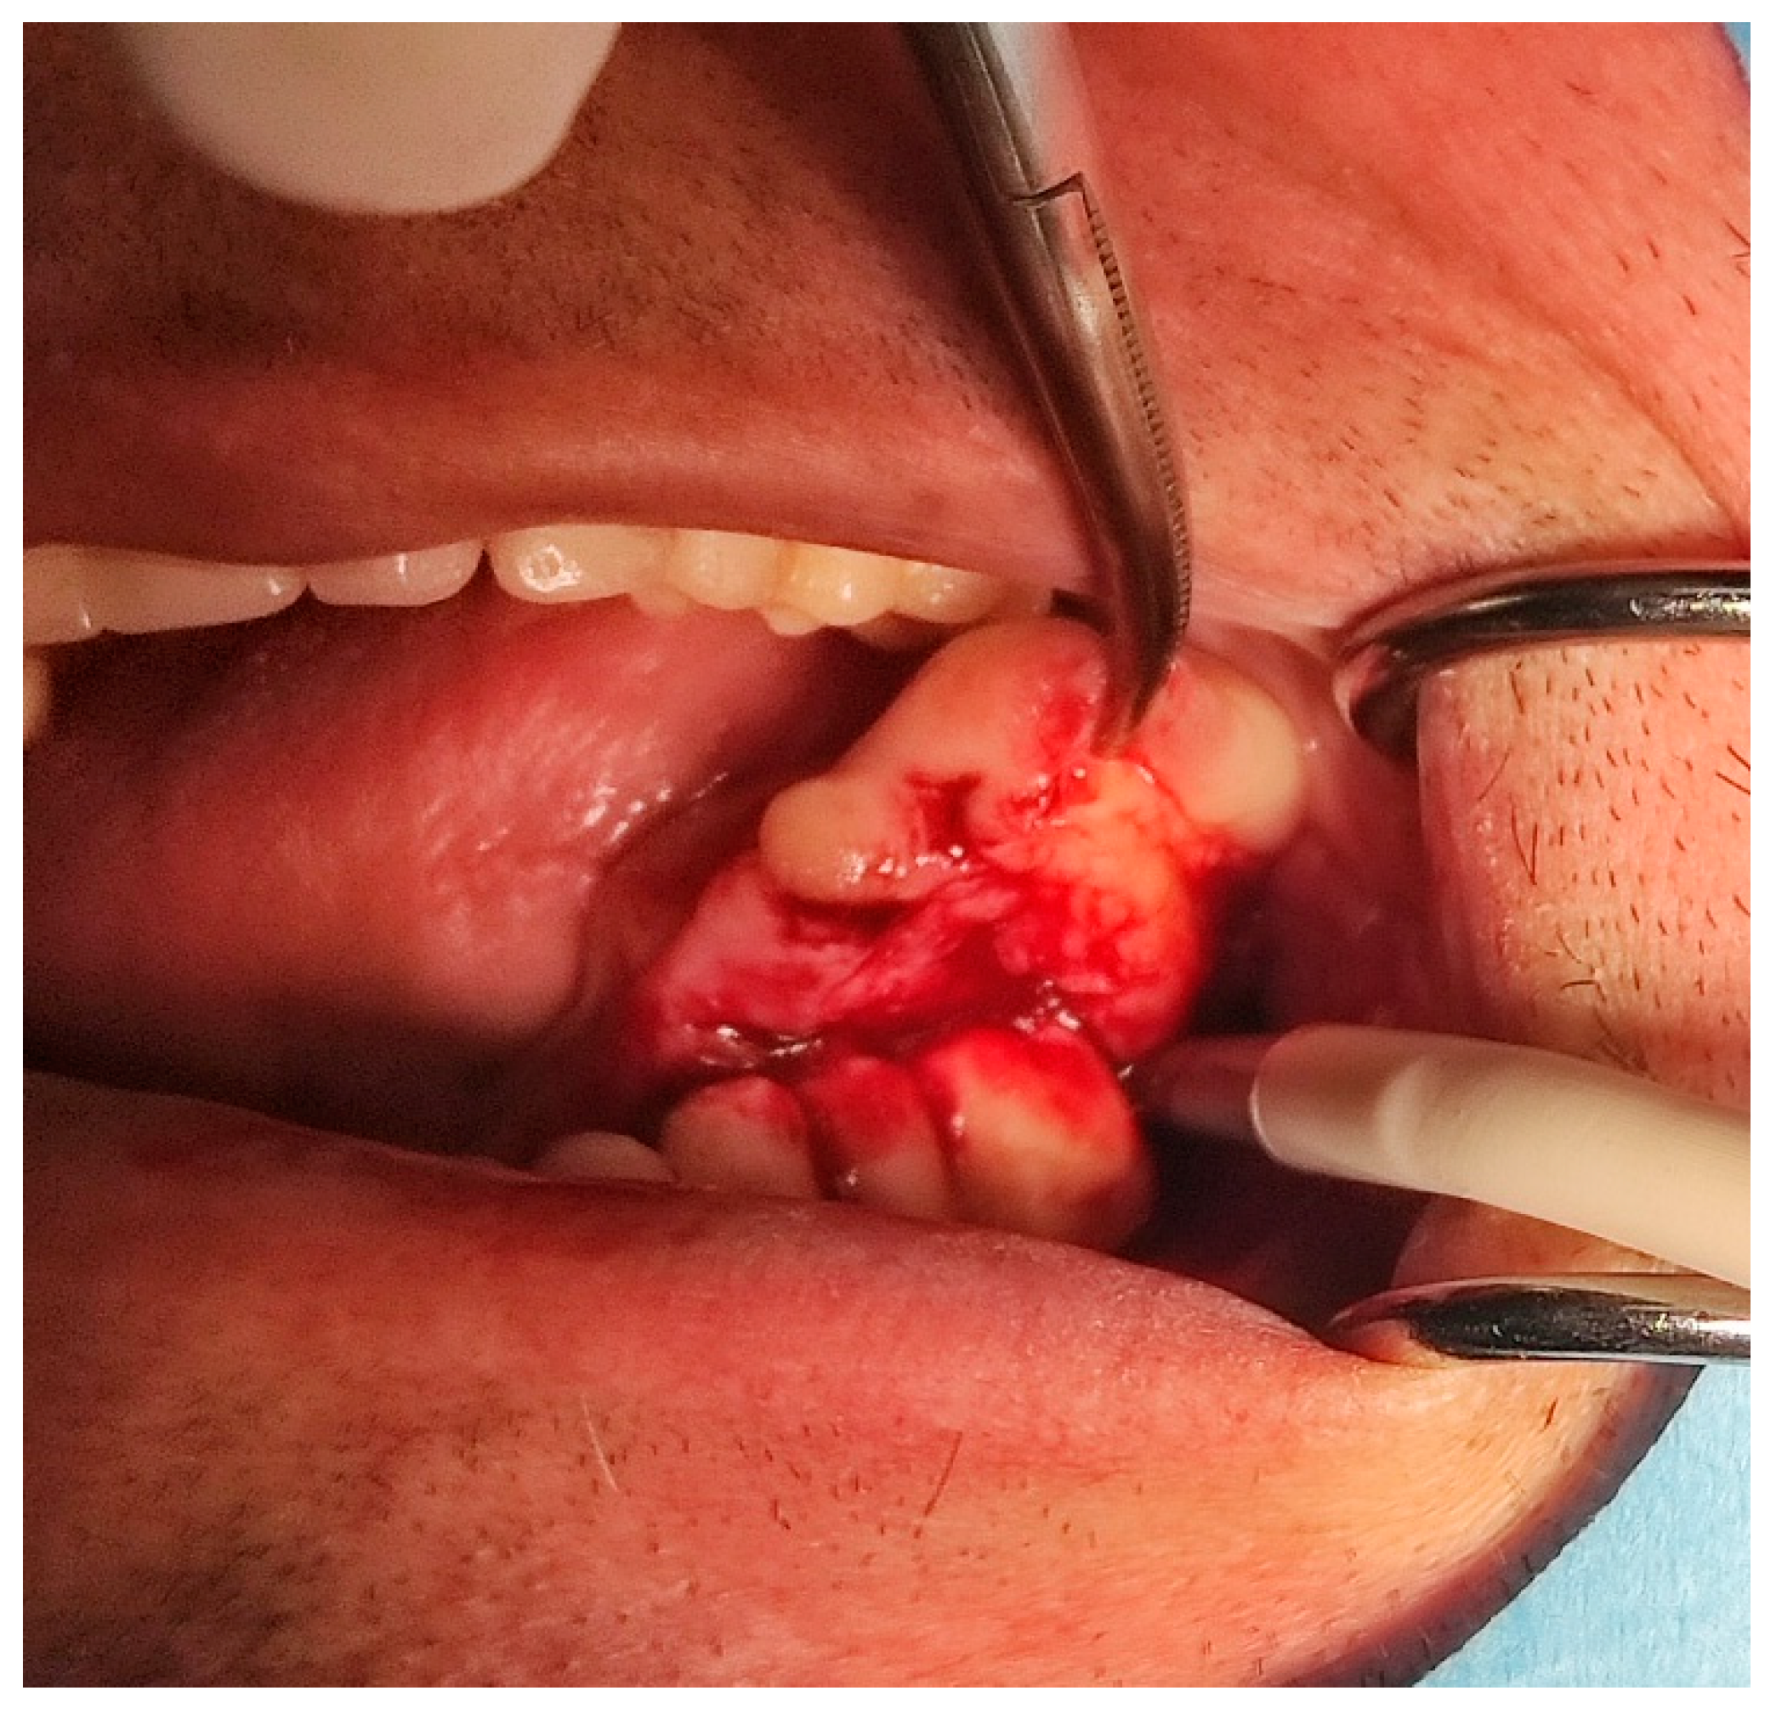

A male 70-year-old patient came to the Department of Oral Surgery, University Hospital Centre Zagreb with a voluminous fibrous mass in the distal region of the left mandible (Figure 1). The patient has two acrylic bridges on four implants. The implants were placed six months prior to admission to the clinic, before the patient noticed the appearance of the mass. The acrylic bridges are 3 months old. The patient states feeling “swelling in the back part of the left mandible three months before coming in for a checkup”. Panoramic radiograph and CBCT did not show any radiolucency, radiopaque areas or signs of periimplantitis around the implants in the bone (Figure 2). The lesion has a smooth surface, with no ulcerations. It was on a broad base connected, with the sublingual anatomical region. The patient has poor oral hygiene, smokes and consumes alcohol: about two to three glasses of wine or beer a day. The palpation of the mass indicated that it was fixed to the alveolar crest of the left mandible on a wide base and was spreading to the left sublingual area. The measured size of the mass was 3.5 × 2 cm. After conducting a clinical examination, the differential diagnosis was possible irritation fibromatosis, peripheral gigantocellular fibroma or peripheral ossifying or non-ossifying fibroma, as well as a malignant mass, and the final diagnosis will be reached after the final PHD analysis. The final decision was an excision in toto (Figure 3). The mass was approached and the layers of submucosa were divided with a scalpel and an electro knife. During operation, it was noticed that the mass has a belonging artery connected to the left sublingual area. The artery was ligated with a resorbing thread 4/0 and the mass underwent complete excision (Figure 4). Parts of the flap were left to heal per secundam, but most of the incision towards the sublingual region was stitched with a non-resorbing silk thread 4/0 (Figure 5 and Figure 6). A full hemostasis was achieved by electrocauterization of the bleeding areas. The excison was performed under local anesthesia. Clinical, medical examination and removal of sutures were performed seven days after surgery (Figure 7).

Figure 1. Clinical appearance of the mass during first visit.